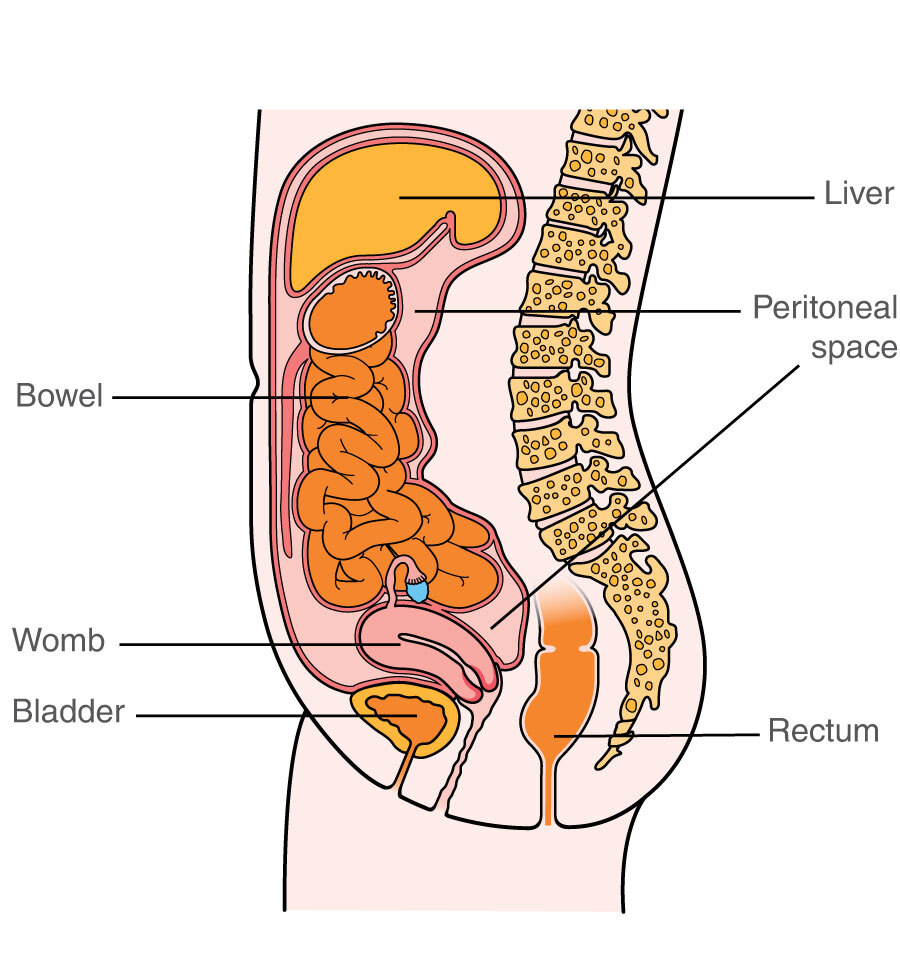

Anatomy Of Internal Organs Female – Organ Anatomy Female Anatomy …

Right Side Women’s Body Human Body Organs / Human Anatomy And …

Female Body Organs Diagram Anatomy | MedicineBTG.com

Human Anatomy Picture Organs Female Human Body Diagram Of Organs See …

Right Side Women’s Body Human Body Organs : What Do Right-Sided Organs …

Female Human Organs Diagram | MedicineBTG.com

Female Abdominal Anatomy Images . Female Abdominal Anatomy Images …

Female Abdominal Anatomy Pictures – koibana.info | Anatomy organs …

Internal Organs Adult Female Front And Back View Stock Photo – Download …

Illustration Of Female Internal Organs Photograph by Science Source

Illustration Of Female Internal Organs Photograph by Science Source

Illustration Of Woman\’S Internal Organs / Internal Human Organ Ovaries …

Human Female Organ Diagram . Human Female Organ Diagram Colorful Human …